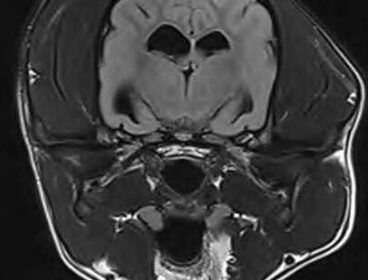

MRI of a dog's brain Learn More